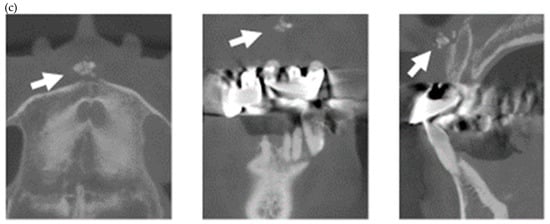

Figure 3.

Multiple external root resorption and calcinosis at the oral region in pt. 4. A dental X-ray photo and CBCT image of teeth and the deposition of calcinosis at the palatal site (a–c). The white arrowhead represents root resorption, the black arrowhead, PDL space widening, and the white arrow, calcinosis, while the black arrow shows a failure to close the space with orthodontic treatment.

In the present study, MERR was detected in four SSc patients, including one described in a case report (pt. 1) [12]. The causes of external resorption, including trauma, periodontal and periapical inflammation, orthodontic treatment, internal bleaching or tumors, were not found in the teeth having external resorption. Dental X-rays and CBCT images showed that MERR was observed in six, six, and four teeth in pts. 2, 3, and 4, respectively (Figure 1a, Figure 2a and Figure 3a). A widening PDL space was detected in all patients. A space between canines and premolars in the upper jaw was found in pts. 3 and 4 (Figure 2a and Figure 3a). Furthermore, the deposition of calcinosis in the nasal spur was noted in pts. 1, [12], 2, and 3, while calcinosis in the palatal plate was observed in pt. 4 (Figure 2c and Figure 3c).